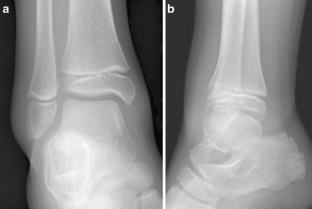

Fig. 2